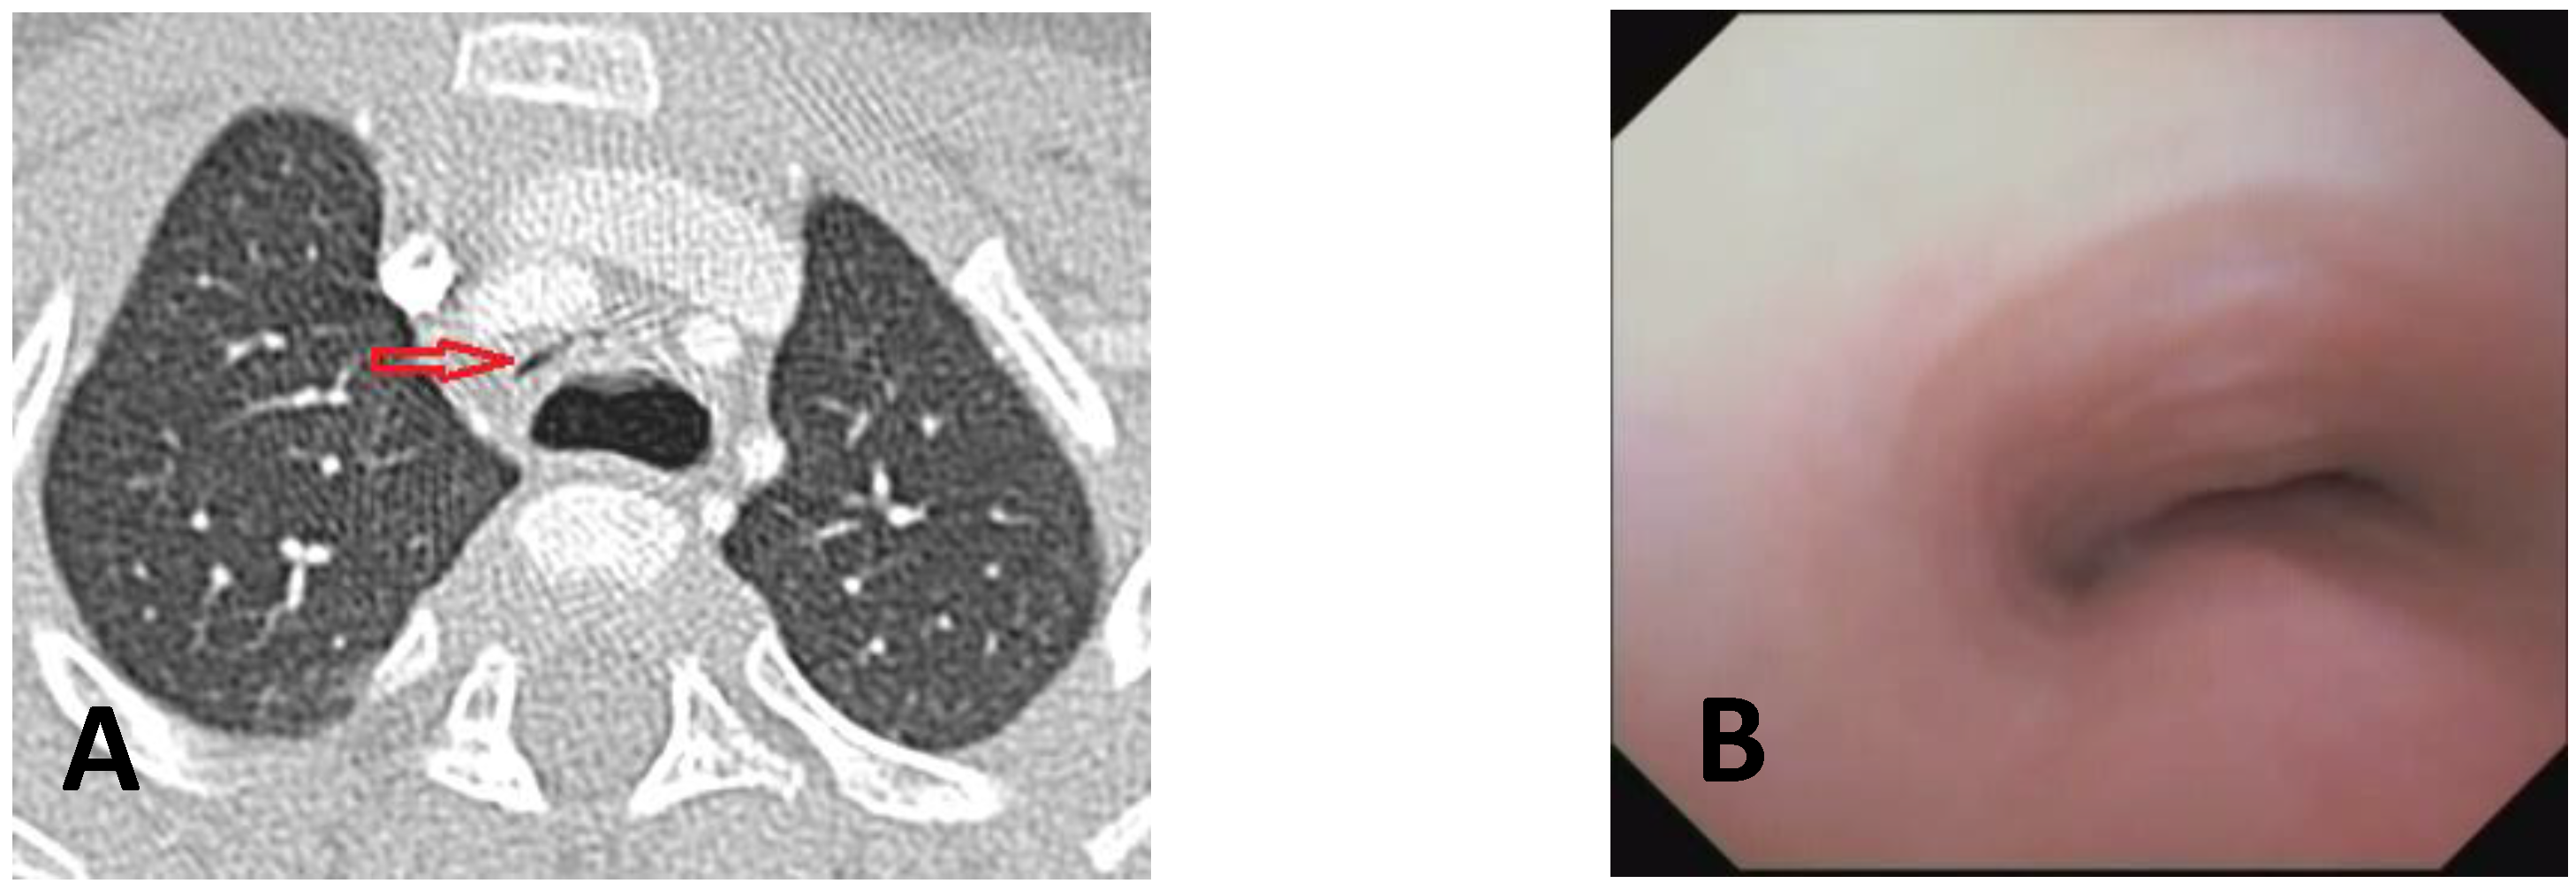

- Computed Tomography (CT): This is a continuously evolving imaging technique, rapid and non-invasive, providing an excellent overall view, independent of body size, with high spatial/temporal resolution. It allows multiplanar and volumetric reconstructions (MPR, MinPR, MipPR, and Volumetric 3D). It can be performed on children of all ages; anesthesia/sedation may be necessary under 5 years of age. Flash Monophasic Technique performed with a single scan, after intravenous injection of CM, provides information on airway morphology (but not dynamics), visualizing airways even distal to the site of obstructions and on mediastinal vessels exerting compression on the trachea or bronchi, highlighting any mediastinal pathology. CT shows cardiovascular anomalies compressing the airway, such as right aortic arch, complete/incomplete double aortic arch, pulmonary sling, and aberrant IA, all causing more or less severe TBM [16]. TM is very frequently associated with EA; CT can demonstrate malacia and extrinsic tracheal compression with a significant reduction in the tracheal ADP at the point of intersection with IA. CT can also demonstrate irreversible lung damage, such as bronchiectasis formation, caused by chronic recurrent lung infections resulting from reduced mucociliary clearance in TBM. Skeletal anomalies (e.g., pectus excavatum and scoliosis) that can cause airway compression and consequent TBM are also demonstrated. CT also evaluates tracheal compressions caused by space-occupying mediastinal lesions. Virtual bronchoscopy obtained with 3D airway reconstruction on CT images has not been very sensitive (<75%) in detecting TBM [17,18].

- Dynamic CT (DCT) allows visualization of the entire airway in a single gantry rotation using a dynamic volumetric scanning technique. Images can be acquired over one or two respiratory cycles with a total scan time of less than 2 s, while the child is breathing at tidal volume during this rapid acquisition. Anesthesia is not necessary, making the exam comfortable and drastically reducing patient discomfort. Dynamic imaging throughout the respiratory cycle allows accurate determination of end-inspiration/end-expiration phases in three dimensions (3D), with accurate determination of luminal collapse degree. The disadvantage of this technique is increased radiation dose to the patient, so it is performed only in selected cases [19,20].